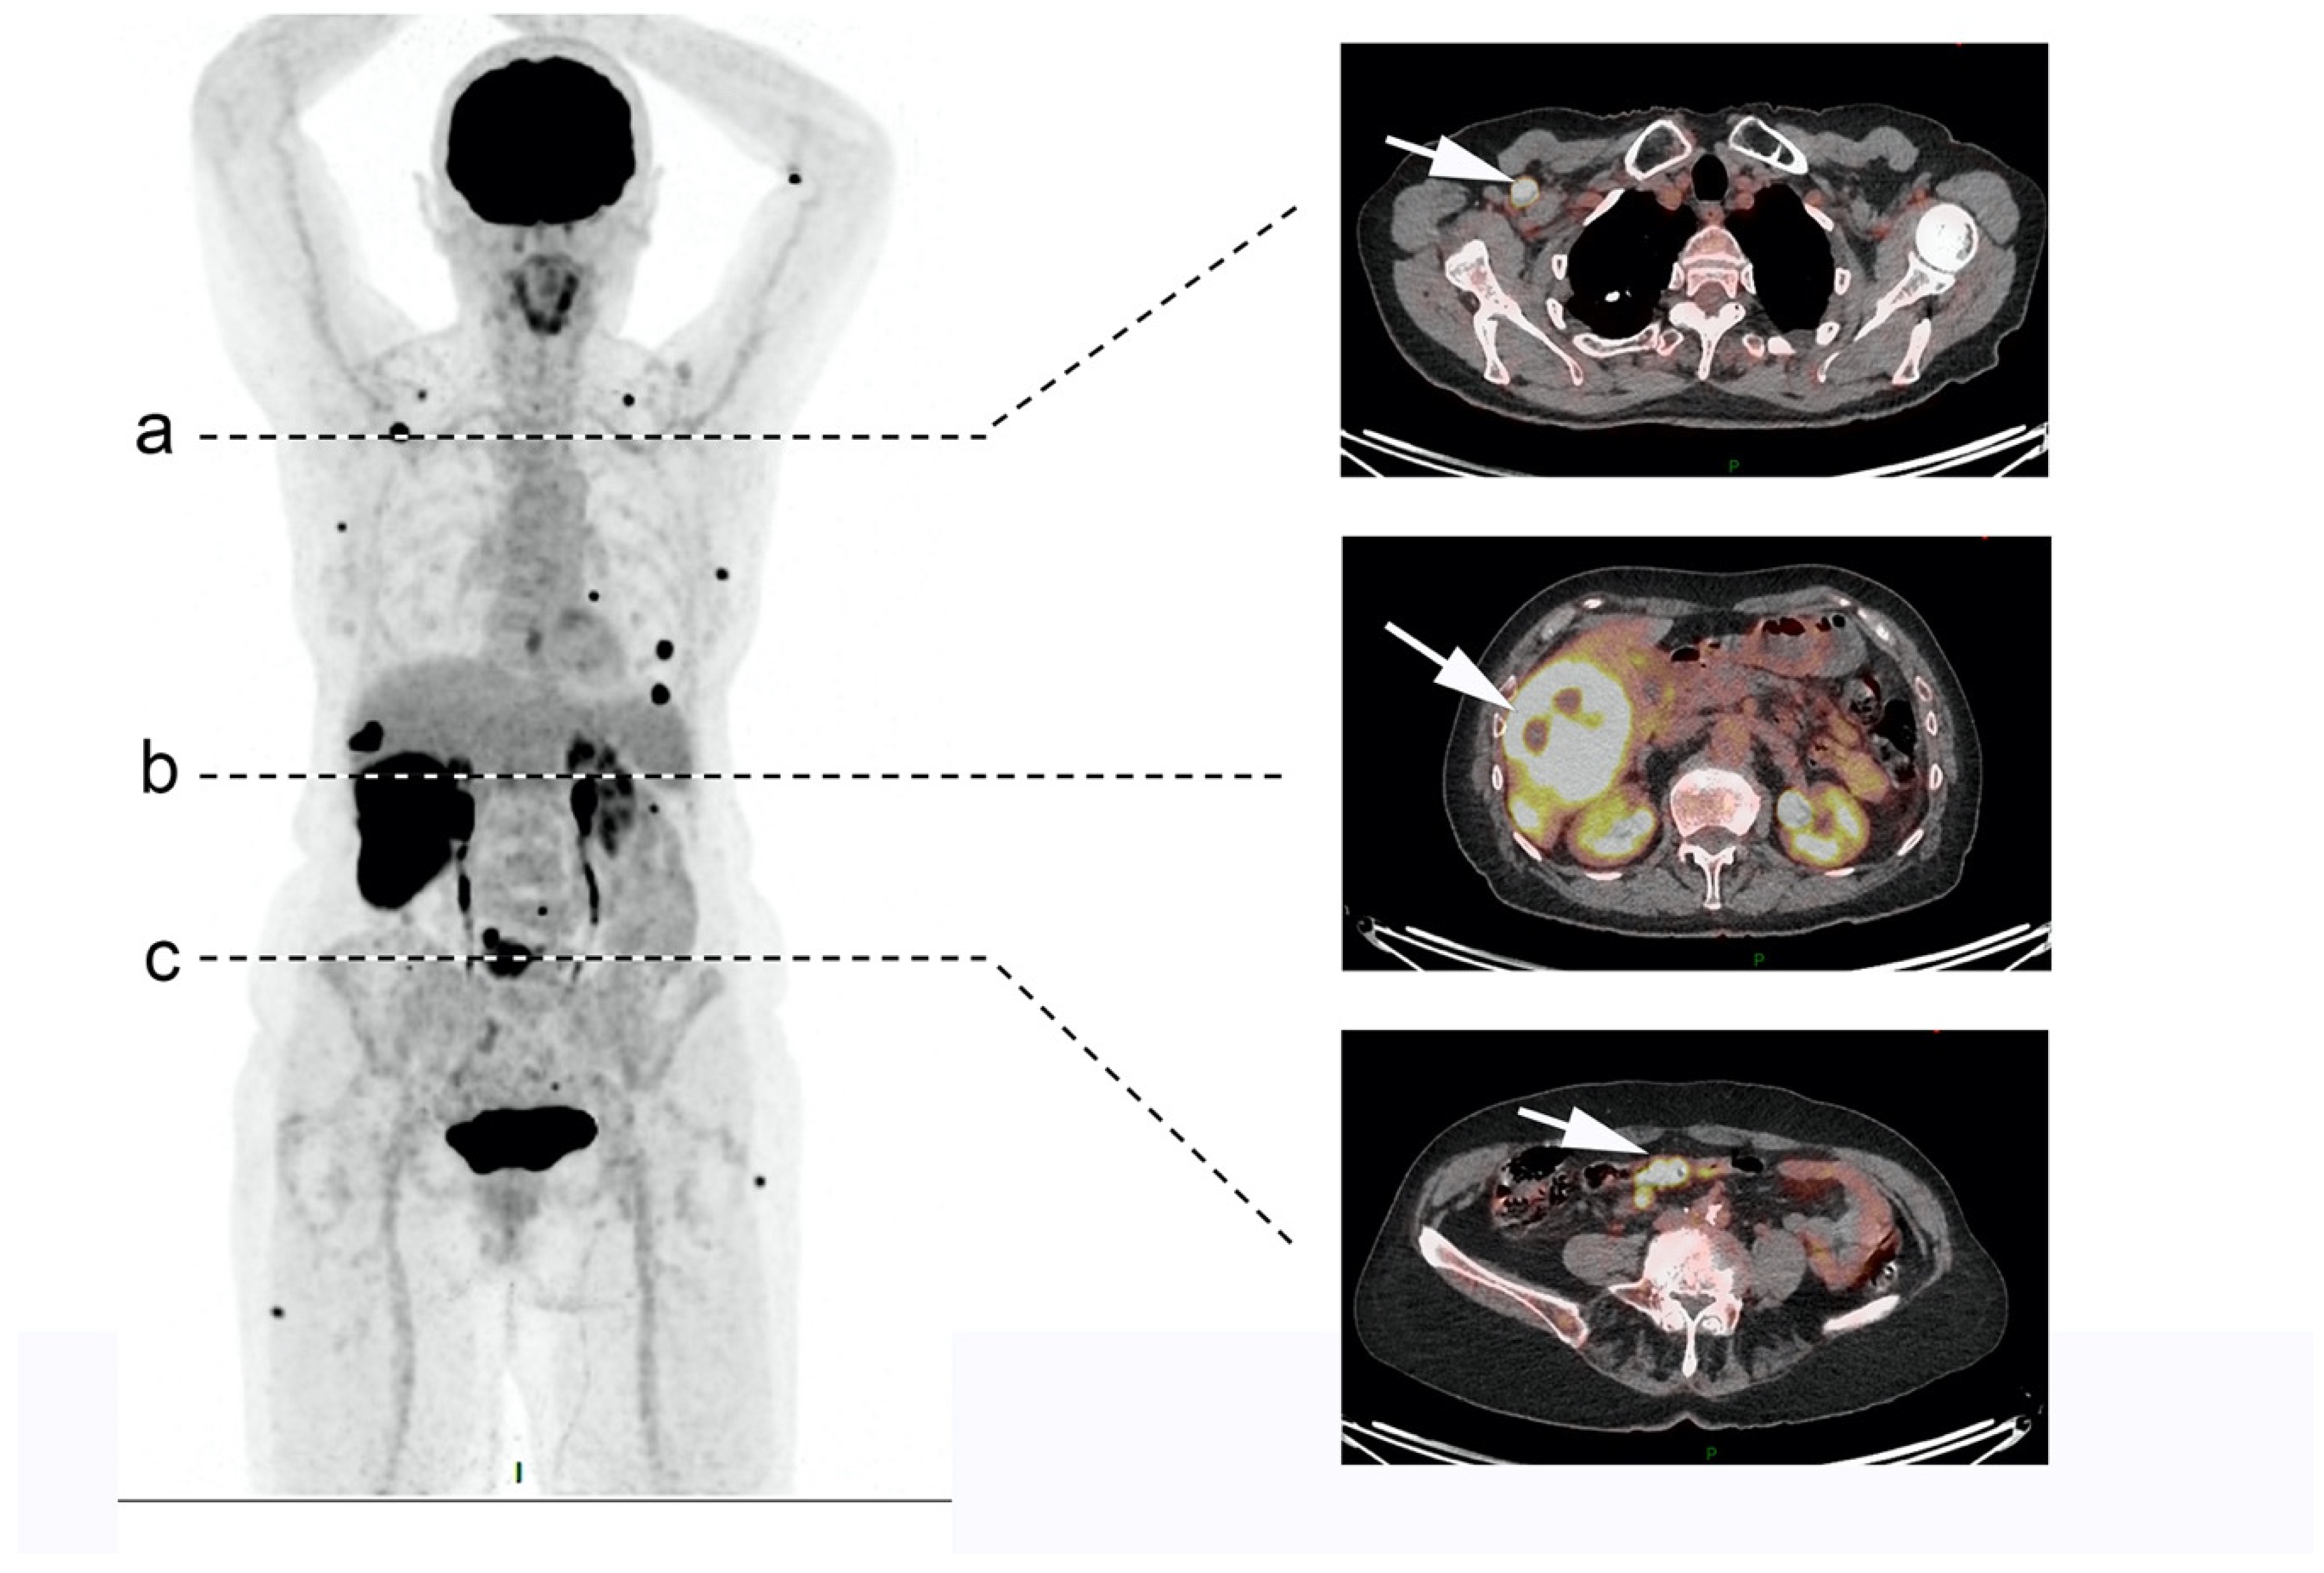

- Zhang, P.; Yu, J.; Li, J.; Shen, L.; Li, N.; Zhu, H.; Zhai, S.; Zhang, Y.; Yang, Z.; Lu, M. Clinical and Prognostic Value of PET/CT Imaging with Combination of 68Ga-DOTATATE and 18F-FDG in Gastroenteropancreatic Neuroendocrine Neoplasms. Contrast Media Mol. Imaging 2018, 2018, 2340389. [Google Scholar] [CrossRef]

- Binderup, T.; Knigge, U.; Loft, A.; Federspiel, B.; Kjaer, A. 18F-Fluorodeoxyglucose Positron Emission Tomography Predicts Survival of Patients with Neuroendocrine Tumors. Clin. Cancer Res. 2010, 16, 978–985. [Google Scholar] [CrossRef]

- Chan, D.L.; Pavlakis, N.; Schembri, G.P.; Bernard, E.J.; Hsiao, E.; Hayes, A.; Barnes, T.; Diakos, C.; Khasraw, M.; Samra, J.; et al. Dual Somatostatin Receptor/FDG PET/CT Imaging in Metastatic Neuroendocrine Tumours: Proposal for a Novel Grading Scheme with Prognostic Significance. Theranostics 2017, 7, 1149–1158. [Google Scholar] [CrossRef]